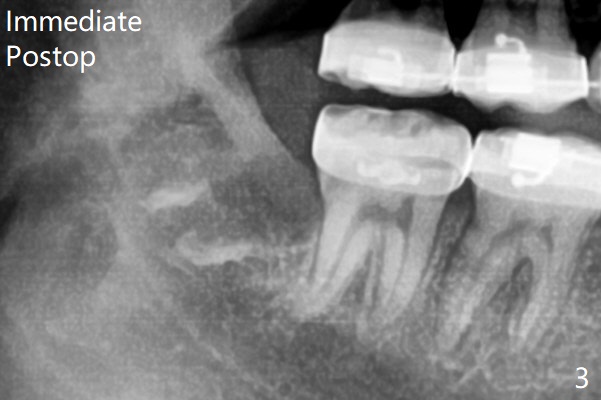

1.5年智齿牙根长长(图二)。1.5月后下颌智齿拔除放置Osteogen Plug(图三)。